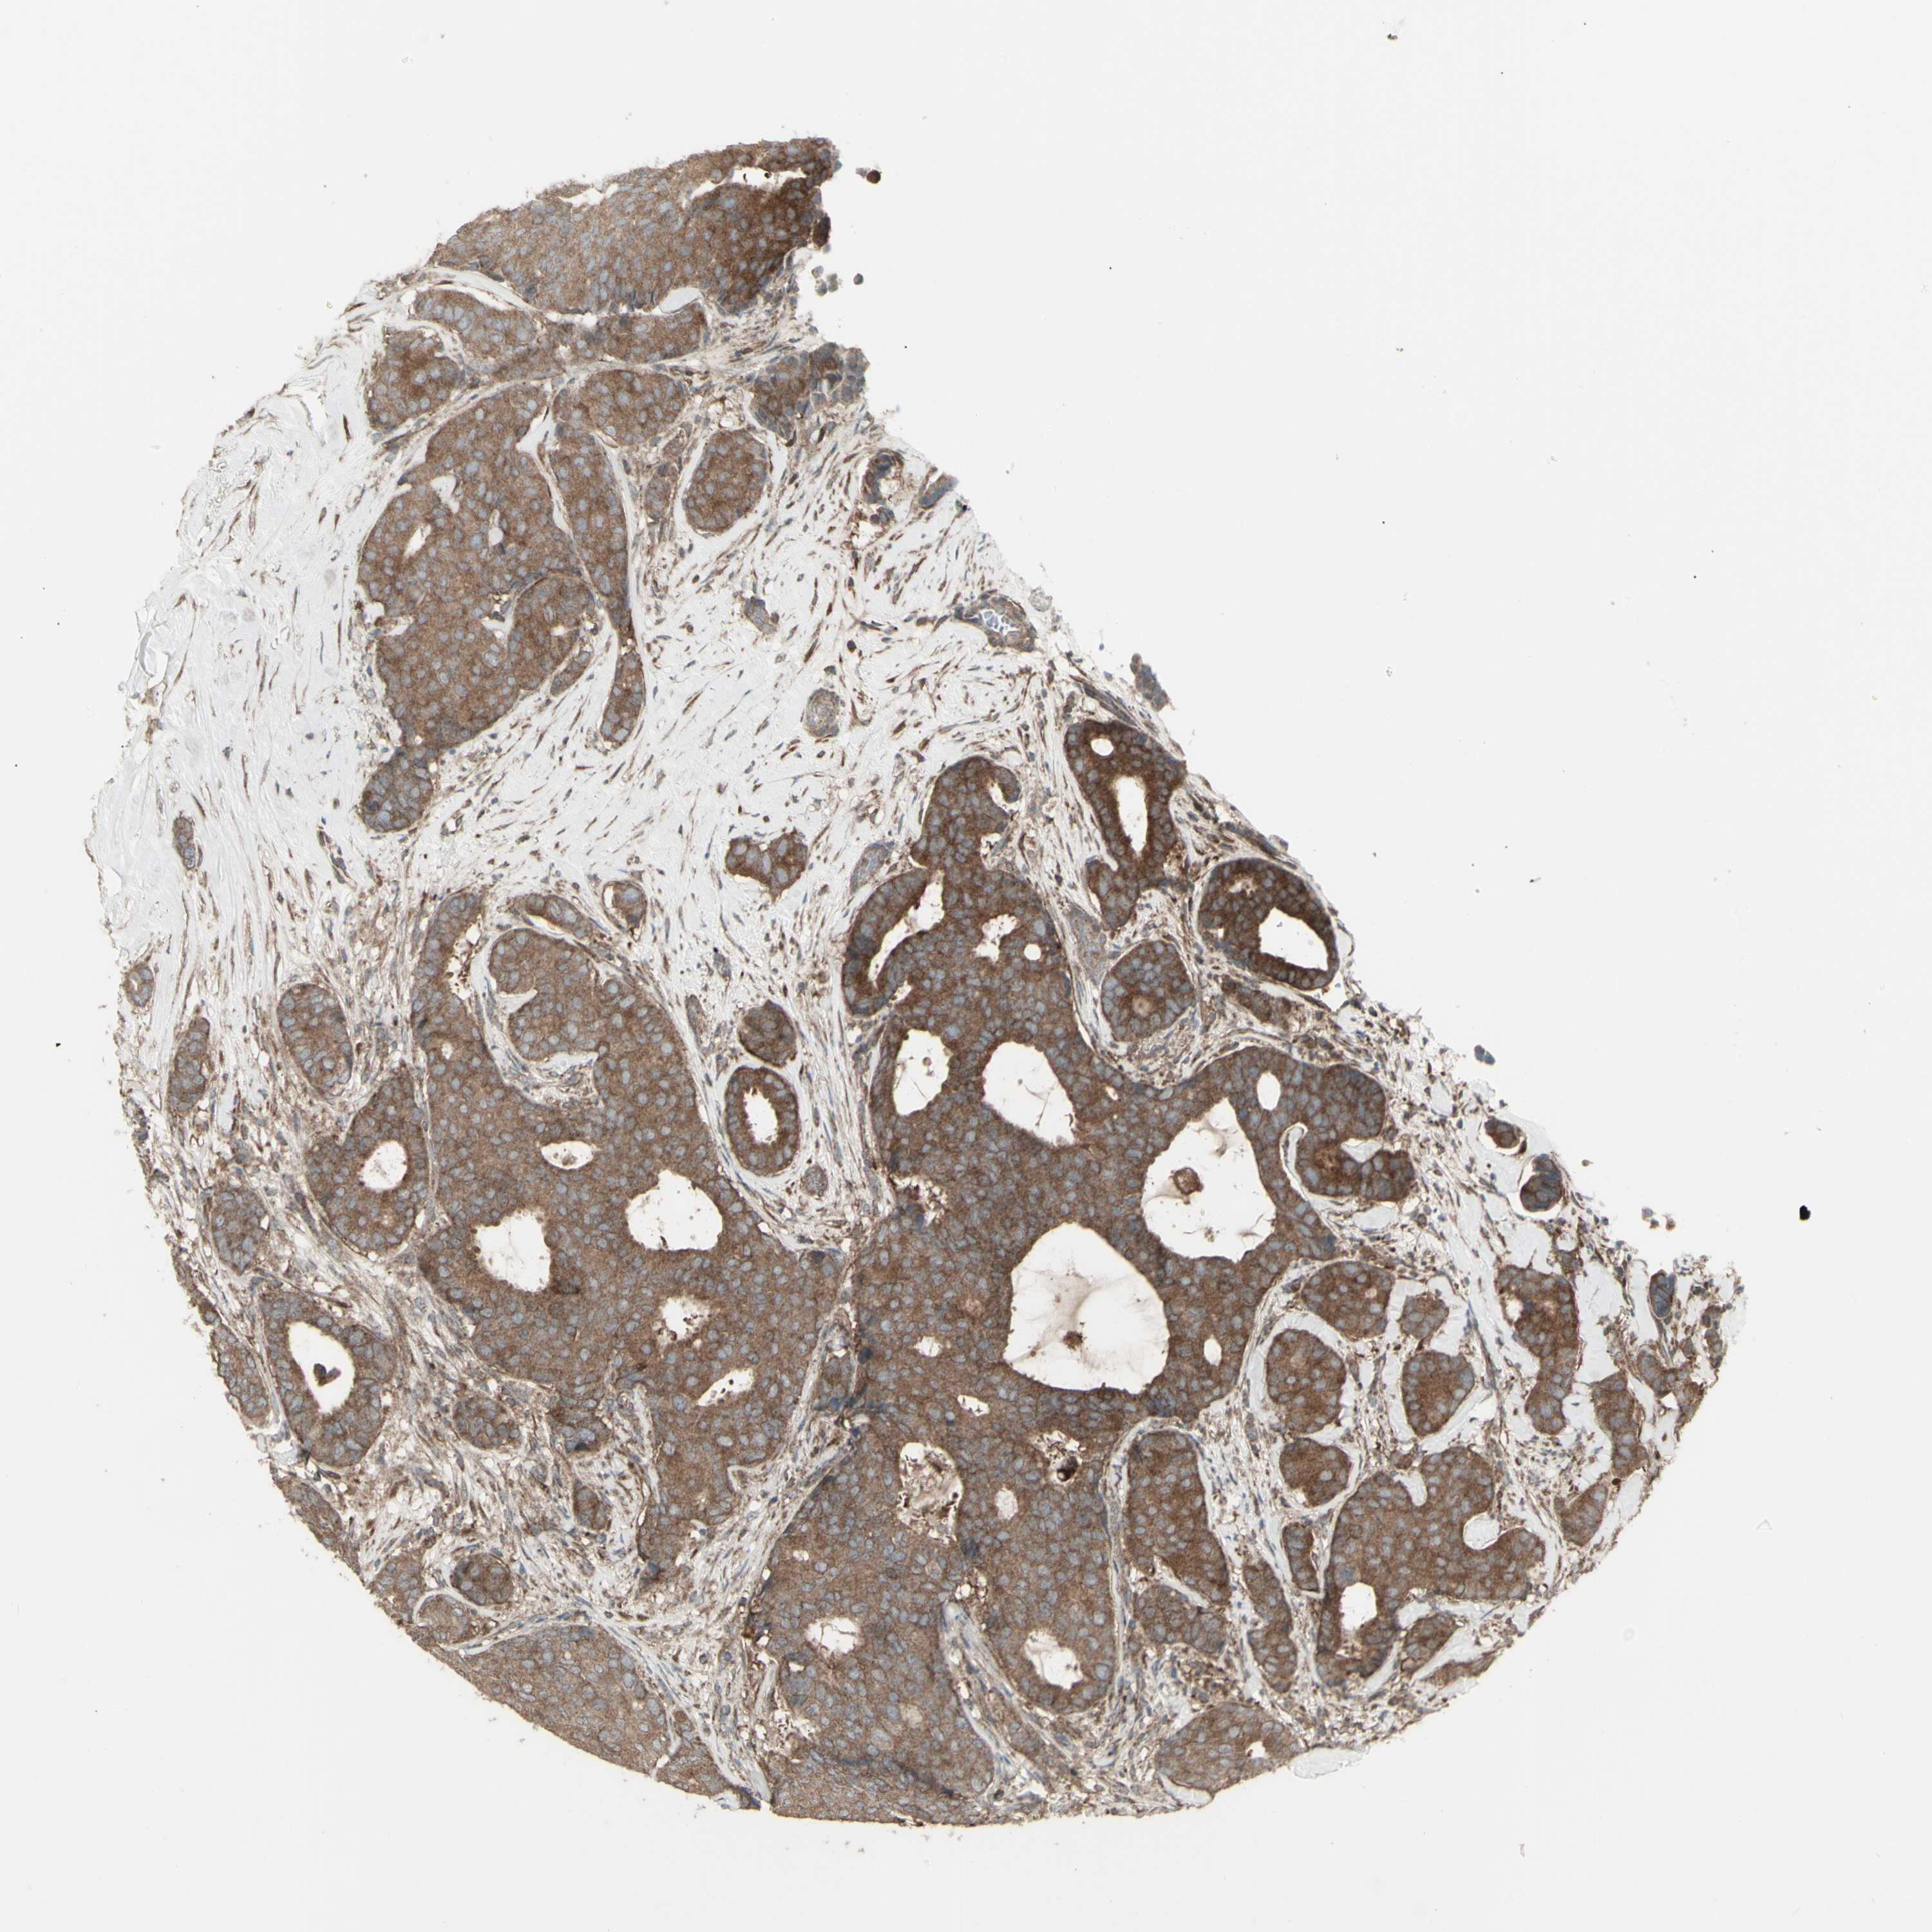

BRCA TCGA BRCA VALIDATION PROTEIN EXPRESSION

ANTIBODIES

AND

VALIDATION